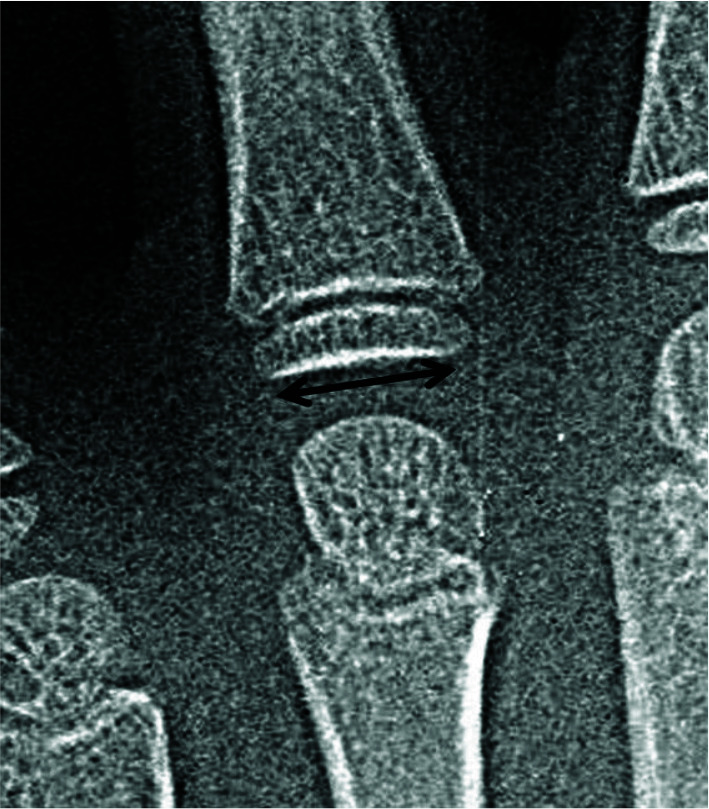

Statement of the problem: Bone age is a more accurate assessment for biologic development than chronological age. The most common method for bone age estimation is using Pyle and Greulich Atlas. Today, computer-based techniques are becoming more favorable among investigators. However, the morphological features in Greulich and Pyle method are difficult to be converted into quantitative measures. During recent years, metacarpal bones and metacarpophalangeal joints dimensions were shown to be highly correlated with skeletal age.

Purpose: In this study, we have evaluated the accuracy and reliability of a trained neural network for bone age estimation with quantitative and recently introduced related data, including chronological age, height, trunk height, weight, metacarpal bones, and metacarpophalangeal joints dimensions.